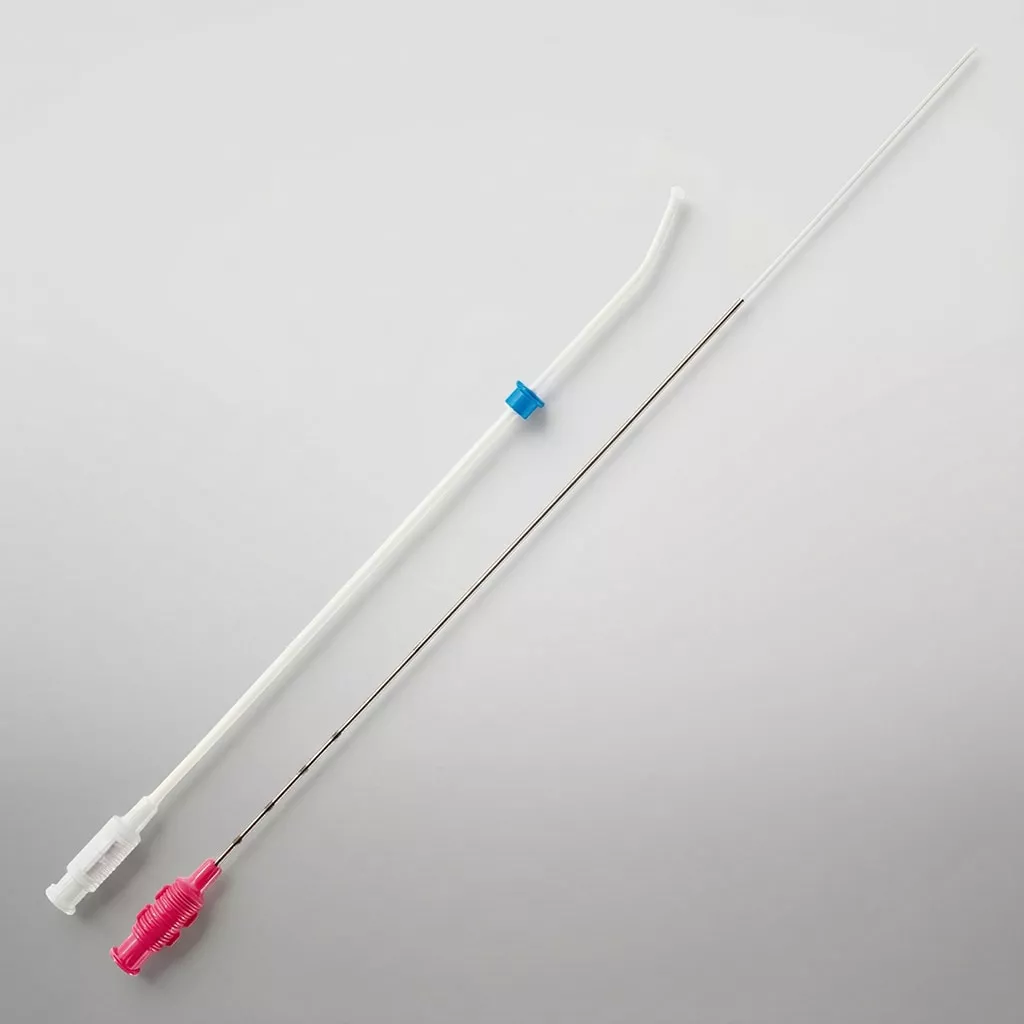

Premium Fas – Single Lumen

Guardia™ Access Nano Embryo Transfer Catheter

Guardia™ Access Embryo Transfer Catheter with Internal Support Cannula

Guardia™ Obturator

Guardia™ Access Malleable Obturator

Soft-Pass™ Malleable Obturator

Guardia™ AccessET Embryo Transfer Catheter

Guardia™ Access Embryo Transfer Catheter

Disposable EchoTip® Amniocentesis Needle

Oocyte Aspiration Needle